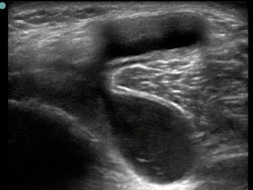

Knee Baker’s Cyst 1 Image